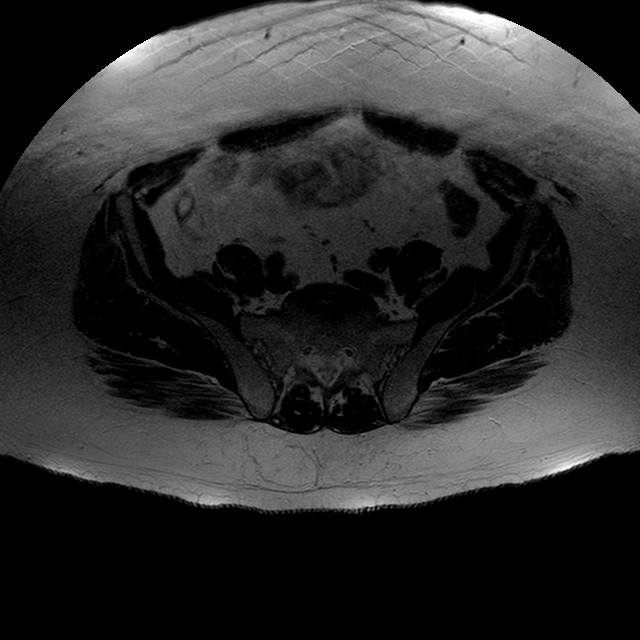

Esami: RMN BACINO

T2w TSE

Evidenti e simmetriche alterazioni osteofitosiche in regione coxo femorale con riduzione delle rime articolari. Degenerazione completa del cercine glenoideo. Non attuali segni di versamento articolare. Non segni di edema osseo che escludono attuale algodistrofia od osteonecrosi. Lieve e simmetrica riduzione del trofismo della muscolatura glutea.